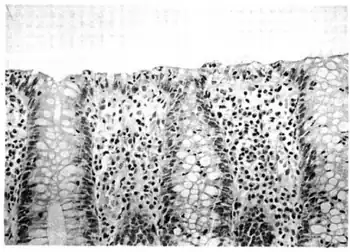

| Micrograph of lymphocytic colitis. HPS stain. | |

The colonoscopy is normal but histology of the mucosal biopsy reveals an accumulation of lymphocytes in the colonic epithelium and connective tissue (lamina propria). Collagenous colitis shares this feature but additionally shows a distinctive thickening of the subepithelial collagen table.[1][2]